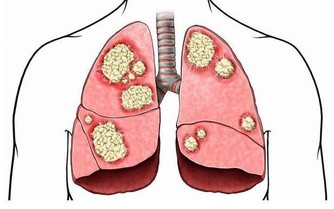

但事實上並非如此,醫生表示說,那是2顆巨大腫瘤,在她的肚子裡面,更可怕的是!

她不僅讓它們在她肚子兩年半,而且也讓她的內臟慢慢被粉碎!

結果醫生一照超音波就發現事情不對勁了,

因為那是非常大顆的腫瘤,而且體積大到像是在肚子懷3個小孩一樣!